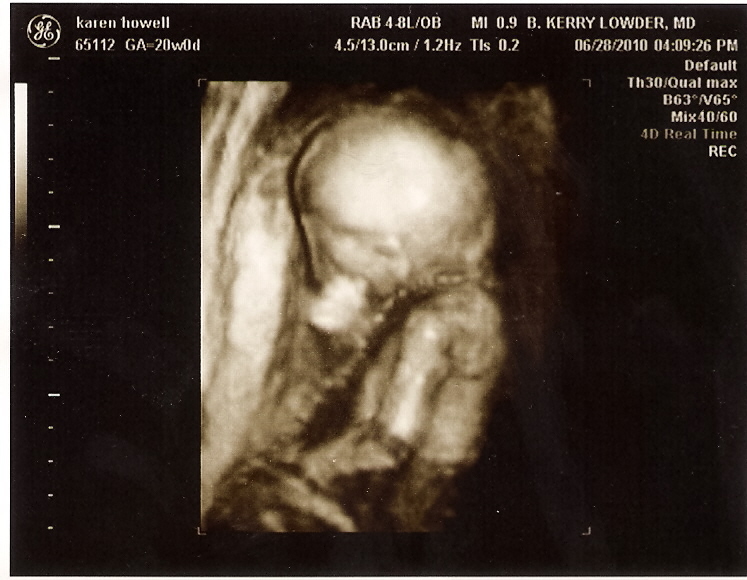

That's right--another little boy. I'm thrilled to be having another boy, but I have to admit I've shed quite a few tears since yesterday at the thought of not having another little girl. Most of all, I'm relieved to find out that he looks HEALTHY. I have been so worried with this pregnancy that there would be problems with the baby. I mean, I've had 5 perfectly healthy babies, I feared I was running out on good luck and we might have problems this time (plus I'm older, on medications, was sooo sick in the beginning, etc.). But, he looks great. My doctor (who I LOVE and has delivered all 5 of my kids) was very good about talking me through each step of the ultrasound to reassure me--"This is the brain, it looks good. This is the heart, it has all four chambers. This is the stomach, it's dark, which means there is fluid in it, which means it can swallow. This is the bladder....".